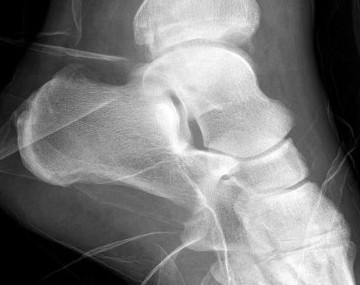

Imaging

Chopart joints

- talonavicular joint

- calcaneocuboid joint